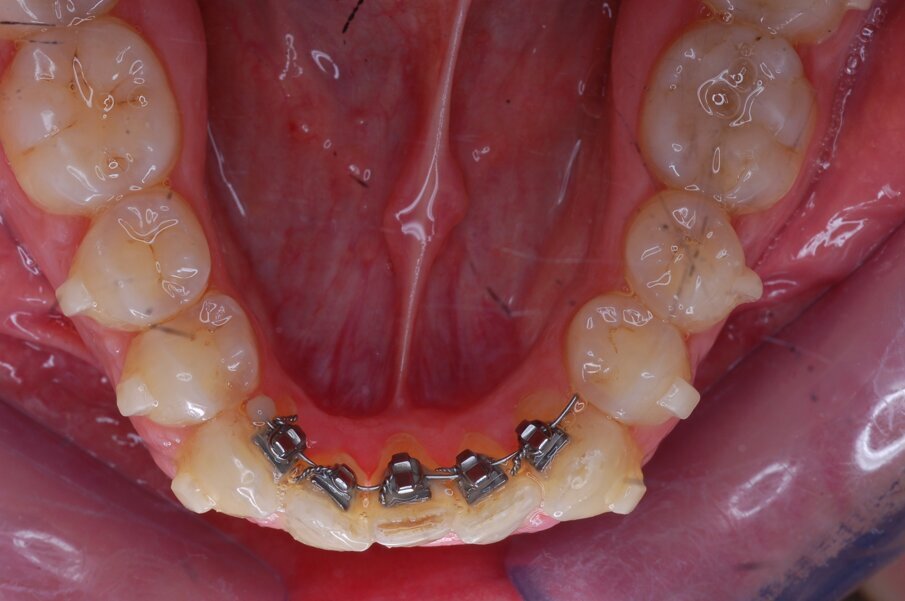

Diagnosi ed eziologia Un uomo sano di 39 anni si è presentato nel nostro studio ortodontico lamentando un aspetto dentale poco attraente e la paura della chirurgia ortognatica proposta da un altro ortodontista. Clinicamente, il profilo del paziente era rettilineo e la vista frontale non mostrava alcuna asimmetria facciale. L’esame funzionale non ha rivelato alcuna deviazione mandibolare o riduzione dei movimenti. Il paziente non aveva dolori articolari e non sono stati rilevati rumori articolari. Era presente una lieve occlusione molare bilaterale di Classe II, un morso aperto e un grave affollamento in entrambe le arcate. L’affollamento era particolarmente grave nell’arcata mandibolare, sebbene mancasse l’incisivo centrale mandibolare destro. Gli incisivi mascellari erano di piccole dimensioni, suggerendo una discrepanza dell’indice di Bolton se fossero stati presenti tutti e quattro gli incisivi mandibolari. Erano inoltre presenti un morso incrociato nella regione dell’incisivo laterale superiore sinistro e una grave rotazione distale del secondo premolare mandibolare sinistro (Figg. 1-8).

Figg. 1-8_Fotografie facciali e intraorali pre-trattamento.

I denti utilizzati come ancoraggio (molari, premolari e canini mandibolari) non presentavano spazi tali per cui gli allineatori si adattassero perfettamente ad essi (Figg. 32, 33). È stato ottenuto un rapido allineamento nella regione anteriore mandibolare in sole nove settimane (Figg. 34-36). Per le fasi finali dell’allineamento è stato inviato un filo Gummetal 0,0175 × 0,0175 in sezione pre-curvata (Figg. 37-50). Dopo 26 mesi, l’ausiliario HAT è stato rimosso e sono stati consegnati al paziente alcuni allineatori di rifinitura per l’allineamento mandibolare conclusivo. Dopo un periodo di trattamento totale di 28 mesi, sono stati eseguiti restauri in composito sugli incisivi mascellari e il paziente ha ricevuto due allineatori di contenzione rigidi da indossare di notte.

Fig. 32_Apparecchio linguale sezionale in posizione.